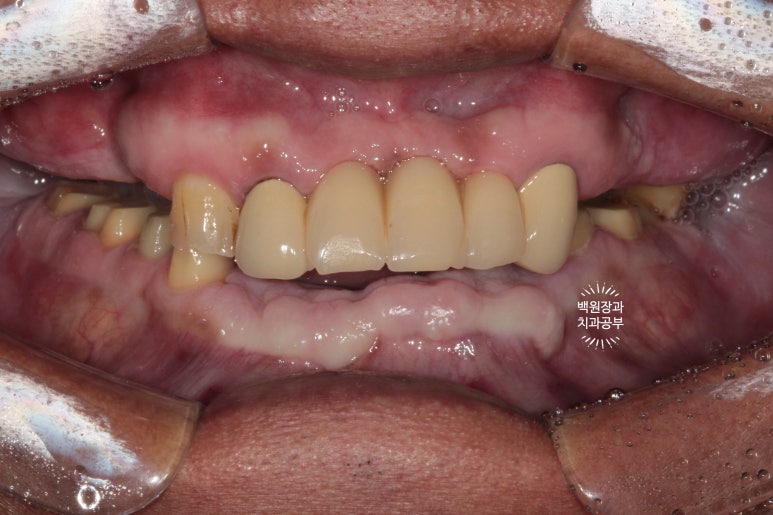

대망의 치료 완료!!!!!

보철물이 모두 완성되었어요.!!!

처음 이를 뽑기 시작한 때부터 정확히 9개월이 지난 시점입니다.

비용의 절감을 위해 기능적으로 문제가 없었던 위 앞니 보철물은 그대로 사용하고 계신 상태라

그 부분이 조금 부족한 느낌은 있지만,

새로 만든 치아들은 아주 조화로운 모양과 색상을 보여주고 있네요!!

아래 어금니 지르코니아 크라운들도 해부학적 형태가 잘 재현되어 있고,

조화로운 모양과 색상으로 거의 자연치와 흡사한 형태를 보여주고 있어요.!!!

식사가 거의 불가했던 환자분이 어금니를 회복함으로 인해 양쪽으로 식사가 가능한 상태가 되셨고,

뿌리만 남아 기능적, 심미적으로 불량했던 아래 앞니는 임플란트 치료를 통해 올바른 길이와 모양으로 재탄생 하였습니다.

저를 믿고 잘 따라와주신 환자분께 감사드리며, 덕분에 아주 좋은 결과로 보답해드릴 수 있어 행복했습니다.